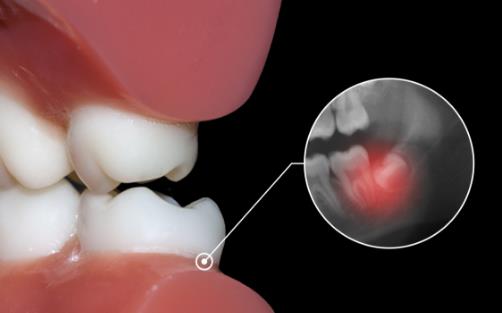

智齒是一個很常見的口腔問題,從現代醫學的觀點看,由于人類食物日益精細,而使用牙齒的磨耗日益減少及咀嚼刺激降低等原因,智齒是人類進化中退變的必然。一旦出現智齒,就需要及時拔除,避免其對口腔造成危害。對于智齒的拔除一般分為兩種情況,一是治療性拔除,一是預防性拔除。下面和360常識網一起來看看吧。

阻生的智齒牙冠周圍軟組織與牙齒之間形成一盲袋,引起食物、細菌的積存,抵抗力下降時,出現冠周炎是必然的。一般的消炎治療治標不治本,因此冠周炎會反復發作。

位置不正的智齒與第二磨牙之間容易積存食物殘渣,而且不易清潔,一般數月可形成齲齒,直接破壞牙體組織。

阻生的智齒往往不能與對頜牙齒建立正常的咬合關系,長時間可導致顳下頜關節彈響、張口疼痛,夜磨牙等癥狀,對青壯年的身心健康影響較大。

有證據表明一些阻生智齒是某些三叉神經痛的病灶所在。

容納牙齒的頜骨不斷退化變小,因而智齒阻生是必然的結果。拔除阻生的智齒對咀嚼、語言等功能無任何不良影響,加之拔除是治療阻生的最有效的辦法,因此,建議盡早、果斷地拔除引起上述危害的阻生智齒。